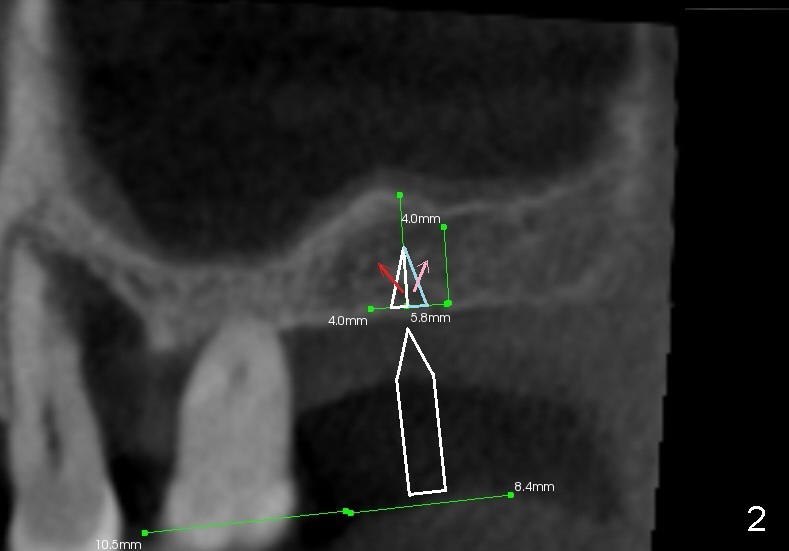

Fig.1 is a sagittal section of the posterior maxilla. A 2 mm (in diameter) round straight osteotome (white box) is going to initiate osteotomy and sinus lift. When the osteotome penetrates the bone initially, the latter is going to be condensed and pushed laterally (mesiodistally) and apically (Fig.2,3 arrows).

As the osteotome advances, some of the bone is brought apically (Fig.3 insert). The tapping with the thin osteotome should be stopped when penetration of the sinus floor is felt. The latter undergoes green stick fracture in a small area (Fig.4 arrows).